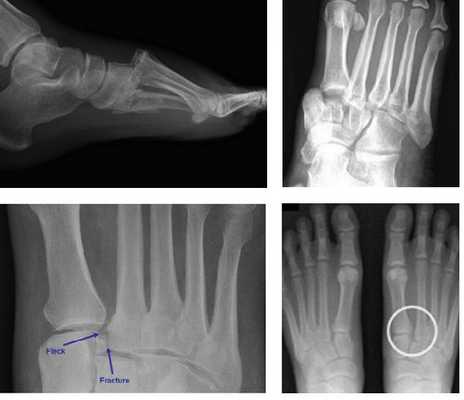

Рентгенологическое исследование

Для диагностики повреждения сустава Шопара делают рентген, КТ и МРТ. На передне-задней рентгенограмме определяют величину пяточно-кубовидного угла. Проводят одну касательную к наружному краю кубовидной кости и вторую касательную к наружному краю пяточной кости. В норме угол между касательными колеблется в пределах от 0 до 5°. Увеличение угла свидетельствует о нарушении стабильности пяточно-кубовидного сочленения. КТ во фронтальной и сагиттальной плоскостях позволяет выявить дефект суставных фасеток, смещение костей при вывихе и фрагментацию костей при переломе. КТ, по сравнению с рентгенографией, является более информативным методом диагностики. МРТ позволяет выявить дефекты отдельных связок.

Рис. 6. Отрывной перелом по тылу таранной кости на границе с суставом Шопара

Рис. 7. Перелом кубовидной кости по передней поверхности

Рис. 8. Переломо-вывих в суставе Шопара

Рис. 9. Переломо-вывих в суставе Шопара

При рентгенографии все снимки выполняются в сравнении со здоровой стопой. Существует несколько основных рентгенологических признаков повреждения сустава Лисфранка. 1. Отсутствие параллельности медиального края основания 2-й плюсневой и медиального края медиальной клиновидной кости 2. Расширение между основаниями 1 и 2 плюсневых костей 3. Наличие костного фрагмента в области основания 2-1 плюсневой кости 4. Тыльный подвывих на боковой проекции 5. Разрыв линии предплюсне-плюсневого сочленения.

У нашей пациентки произошёл гомолатеральный вывих, то есть все плюсневые кости сместились в наружном направлении. На стандартных рентгенограммах в свежих случаях данные повреждения пропускают практически в 100% случаев. Необходимо делать рентгенограммы обеих стоп стоя с нагрузкой весом тела и даже в такой ситуации неопытный глаз пропустит травму.

Лучше - сделать КТ исследование, где в сравнении со здоровой стороной будет очень хорошо видно повреждение.